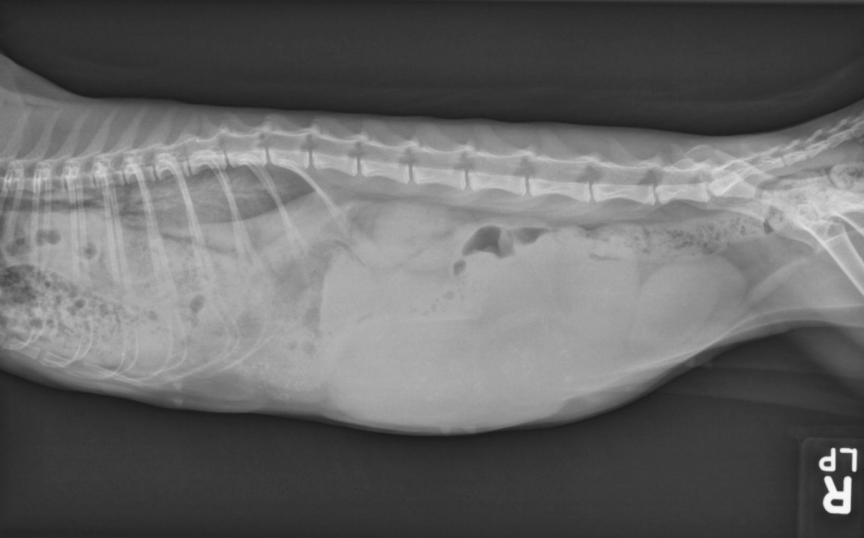

● 7 yo castrated male Golden

Retriever

● Lethargy for last 24h

fat along cranioventral aspect of thorax, maybe fluid too at heart apex.

pericardial effusion: very round heart margin tells you its fluid and not just cardiomegaly.

mild bronchial pattern